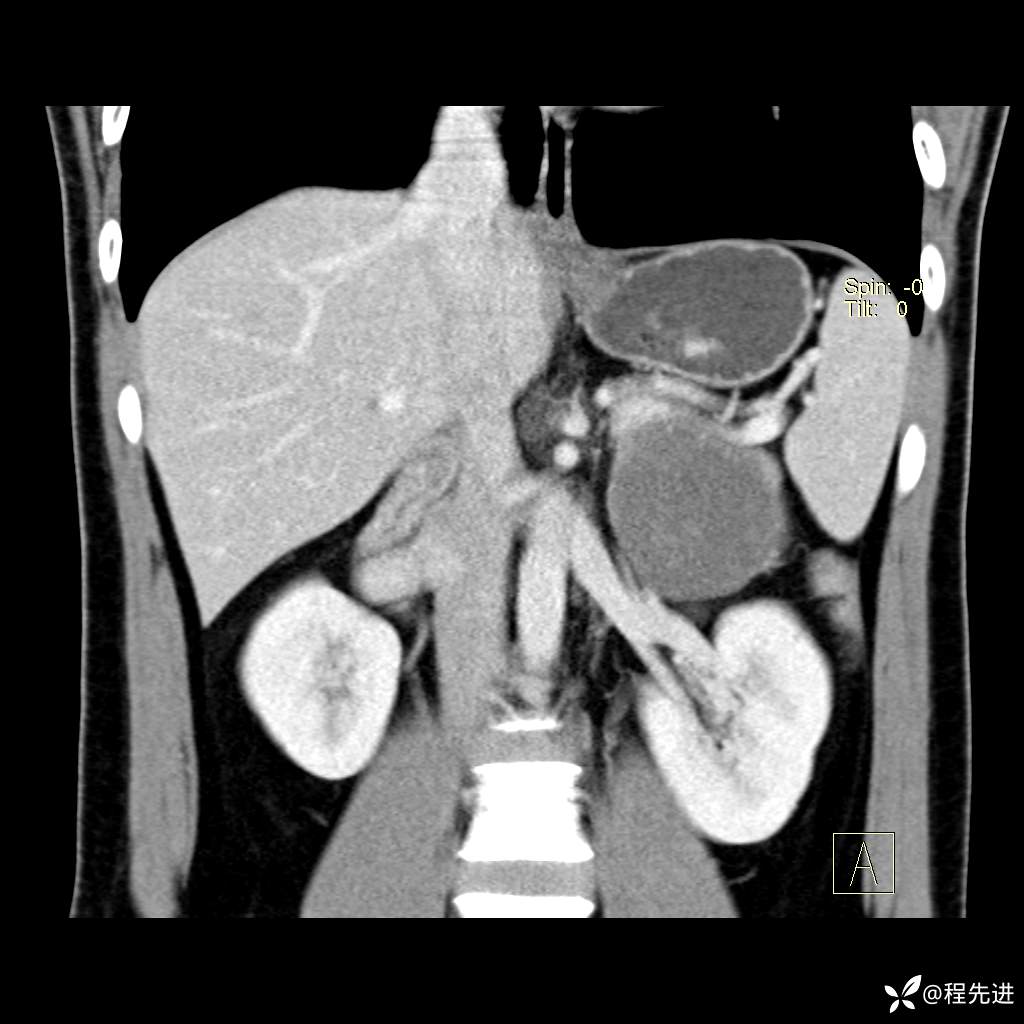

CT平扫:(CT值:平扫,27HU,动脉期,27HU,门静脉期,31HU,平衡期,32HU)

冠状位重建: